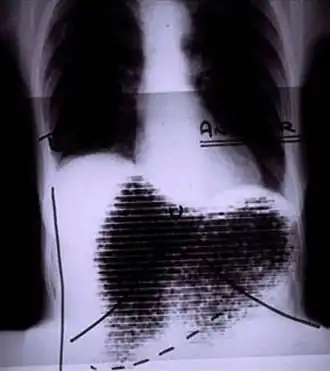

![]() Manual image fusion of x-rayed and rectilinear scanned chest | |

A rectilinear scanner is an imaging device, used to capture emission from radiopharmaceuticals in nuclear medicine. The image is created by physically moving a radiation detector over the surface of a radioactive patient. It has become obsolete in medical imaging, largely replaced by the gamma camera since the late 1960s.[1][2][3]

The patient is administered with a radioactive pharmaceutical agent, such as radio-iodine which will naturally collect in the thyroid. The detector moves in a raster pattern over studied area of the patient, making a constant count rate. A collimator restricts detection to a small area directly below its position so that by the end of the scan emission from the whole study area has been detected. The output method is designed such that positional and detection information is maintained. For example, when using a light source and film the light is moved in tandem with the detector, and the intensity of light produced increases with an increase in activity, producing dark areas on the film.[11][12]